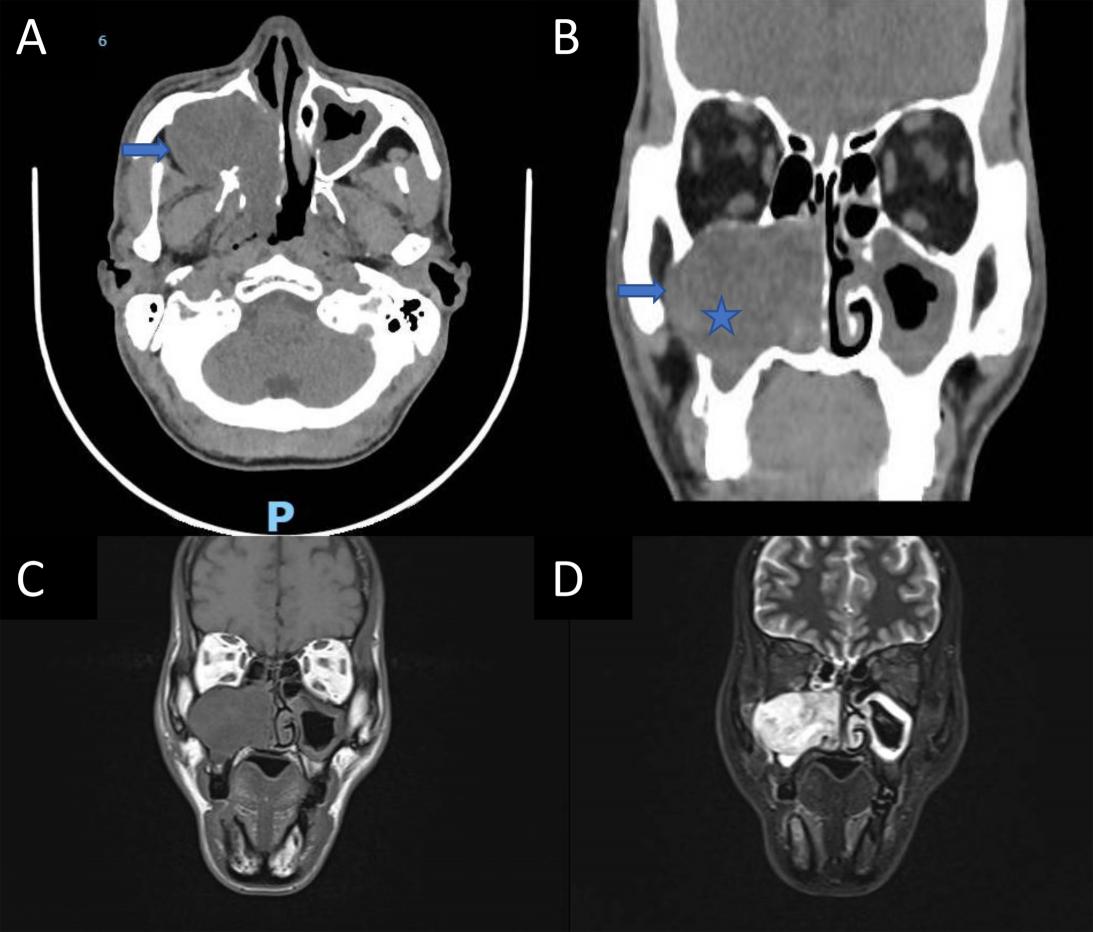

Vừa qua, Khoa Tai Mũi Họng – Mắt - Răng Hàm Mặt, Bệnh viện Trường Đại học Y Dược Huế đã thực hiện phẫu thuật nội soi với đường mổ Denker cải tiến để lấy khối u tế bào quanh mạch mũi xoang cho một bệnh nhân nam 53 tuổi. Bệnh nhân nhập viện vì nghẹt mũi, chảy mũi, giảm khứu giác, đau nhức mặt và chảy nước mắt bên phải trong 6 tháng. Khám nội soi ghi nhận khối u hốc mũi phải đẩy lệch cuốn mũi dưới, chiếm phức hợp lỗ ngách phải, kèm hình ảnh tiêu xương và xâm lấn vào hố dưới thái dương.

Hình 1. Hình ảnh khối u tế bào quanh mạch mũi xoang. A, Hình ảnh chụp cắt lớp vi tính khối u (hình ngôi sao) gây tiêu xương (mũi tên xanh dương); B, Hình ảnh khối u đẩy ổ mắt và xoang hàm; C và D, Hình ảnh cộng hưởng từ khối lan lên xoang sàng và cửa mũi sau